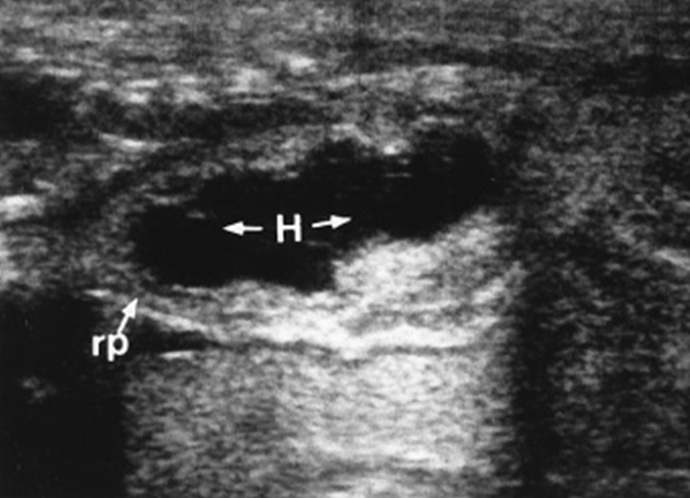

Hydronephrosis - UPJ Obstruction

Hydronephrosis